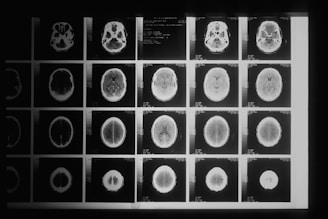

Serviço de segunda opinião e revisão técnica de exames de imagem em Neurorradiologia e Cabeça e Pescoço, com análise criteriosa de Tomografia Computadorizada (TC) e Ressonância Magnética (RM), fundamentada em critérios radiológicos atualizados e correlação clínico-radiológica.